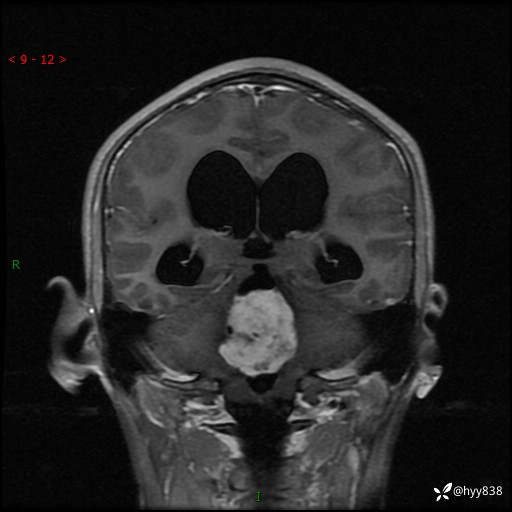

性别:男

年龄:17岁

简要病史:头痛伴间断性呕吐1月余,外院CT提示颅脑占位

颅脑MRI平扫+增强